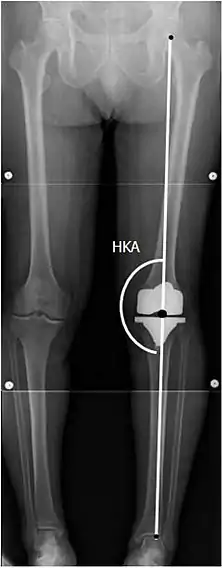

![]() |

Angles commonly measured before knee replacement surgery: |

To indicate knee replacement in case of osteoarthritis, its radiographic classification and severity of symptoms both should be substantial. Such radiography should consist of weightbearing X-rays of both knees: AP, lateral, and 30 degrees of flexion. AP and lateral views may not show joint space narrowing, but the 30-degree flexion view is most sensitive for narrowing. Full-length projections also are used in order to adjust the prosthesis to provide a neutral angle for the distal lower extremity. Two angles used for this purpose are:

- Hip-knee-shaft angle (HKS),[9] an angle formed between a line through the longitudinal axis of the femoral shaft and its mechanical axis, which is a line from the center of the femoral head to the intercondylar notch of the distal femur.[11]

- Hip-knee-ankle angle (HKA),[10] which is an angle between the femoral mechanical axis and the center of the ankle joint.[11] It is normally between 1.0° and 1.5° of varus in adults.[12]